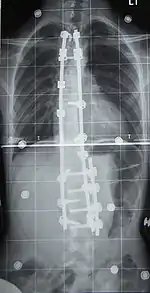

Cirugía

La cirugía se suele indicar en las curvas que tienen una alta probabilidad de progresión (es decir, más de magnitud 45 a 50 grados), las curvas que sería estéticamente inaceptable como un adulto, las curvas en los pacientes con espina bífida y la parálisis cerebral que interfieren con la sesión y la atención , y las curvas que afectan las funciones fisiológicas tales como la respiración.

Cirugía para la escoliosis es realizado por un cirujano que se especializa en cirugía de columna. Por diversas razones, generalmente es completamente imposible enderezar una escoliosis, pero en la mayoría de los casos las correcciones dan muy buenos resultados.

Fusión vertebral con instrumentación

La fusión espinal es la cirugía que más se realiza para la escoliosis. En este procedimiento, el hueso (ya sea cosechado en otras partes del autoinjerto cuerpo o de un injerto de donantes) es injertado en las vértebras de manera que cuando se cura se va a formar una masa ósea sólida y en la columna vertebral se vuelve rígido. Esto previene el empeoramiento de la curva a expensas de algunos movimientos de la columna. Esto puede ser realizado desde la anterior (frontal) los aspectos de la columna vertebral por entrar en la cavidad torácica o abdominal, o más comúnmente realizado desde la parte trasera (posterior). Una combinación se utiliza en los casos más graves.

Los sistemas modernos espinal están tratando de resolver el desequilibrio sagital y sin resolver los defectos de rotación por el sistema de barras de Harrington. Que implican una combinación de varillas, tornillos, ganchos y alambres de fijación de la columna vertebral y puede solicitar más fuerte, más seguro para las fuerzas de la columna vertebral de la barra de Harrington. Esta técnica se conoce como la Cotrel instrumentación Dubousset, actualmente la técnica más común para el procedimiento.